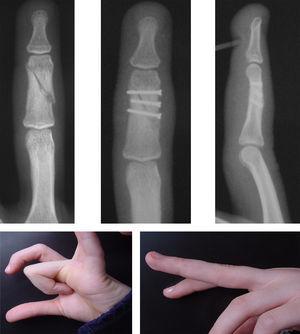

Las reducciones radiográficas de la fractura fueron aceptables desde el punto de vista anatómico en 78 (92,85%) casos. En 3 (3,57%) pacientes con fractura articular de la base de la falange conminuta hubo defecto de reducción de la fractura con una superficie articular corregida, en 2 pacientes (2,38%) no se consiguió corregir perfectamente la superficie articular debido a la gran conminución y a que los fragmentos óseos eran muy pequeños (referidos como malos resultados) y en un (1,19%) paciente con fractura de la falange proximal del cuarto dedo quedó una ligera diástasis del foco de fractura, tras tener un traumatismo en el dedo la fractura se desplazó y se lo intervino para colocarle una placa y tornillos (referido como mal resultado [figura 5).

Figura 5. Fractura oblicua larga de la falange proximal del dedo anular de la mano derecha. Fracaso de osteosíntesis percutánea. Nueva osteosíntesis con placa y tornillos.

Las complicaciones imputables a la técnica solamente se han observado en 3 pacientes, en uno de ellos la fractura no quedó suficientemente estable y al recibir el paciente un traumatismo sobre el dedo se desplazó y movió los tornillos, por lo que precisó una nueva intervención mediante osteosíntesis con placa y tornillos, con buenos resultados posteriores (figura 5). En 2 pacientes no se consiguió la reducción anatómica articular adecuada, aunque probablemente si se hubiera intentado la reducción abierta el resultado habría sido igual o peor debido al tamaño reducido y a la gran conminución de los fragmentos óseos.

Los otros 2 pacientes con malos resultados funcionales fueron una paciente que presentaba una fractura oblicua larga de la falange proximal del dedo medio tratada con 3 tornillos percutáneos que había consolidado en buenas condiciones, pero que debido a la inmovilización prolongada durante 5 semanas presentó una rigidez con defecto de la flexión de la IFP por adherencia de las bandeletas laterales del aparato extensor que se corrigió tras realizar una tenolisis; el otro paciente presentaba una fractura de la base de la falange proximal del dedo meñique tratada con 2 tornillos percutáneos, por falta de movilización precoz del paciente debido a una mala colaboración se decidió realizar una nueva intervención quirúrgica con el fin de liberar adherencias y conseguir una mayor movilidad.